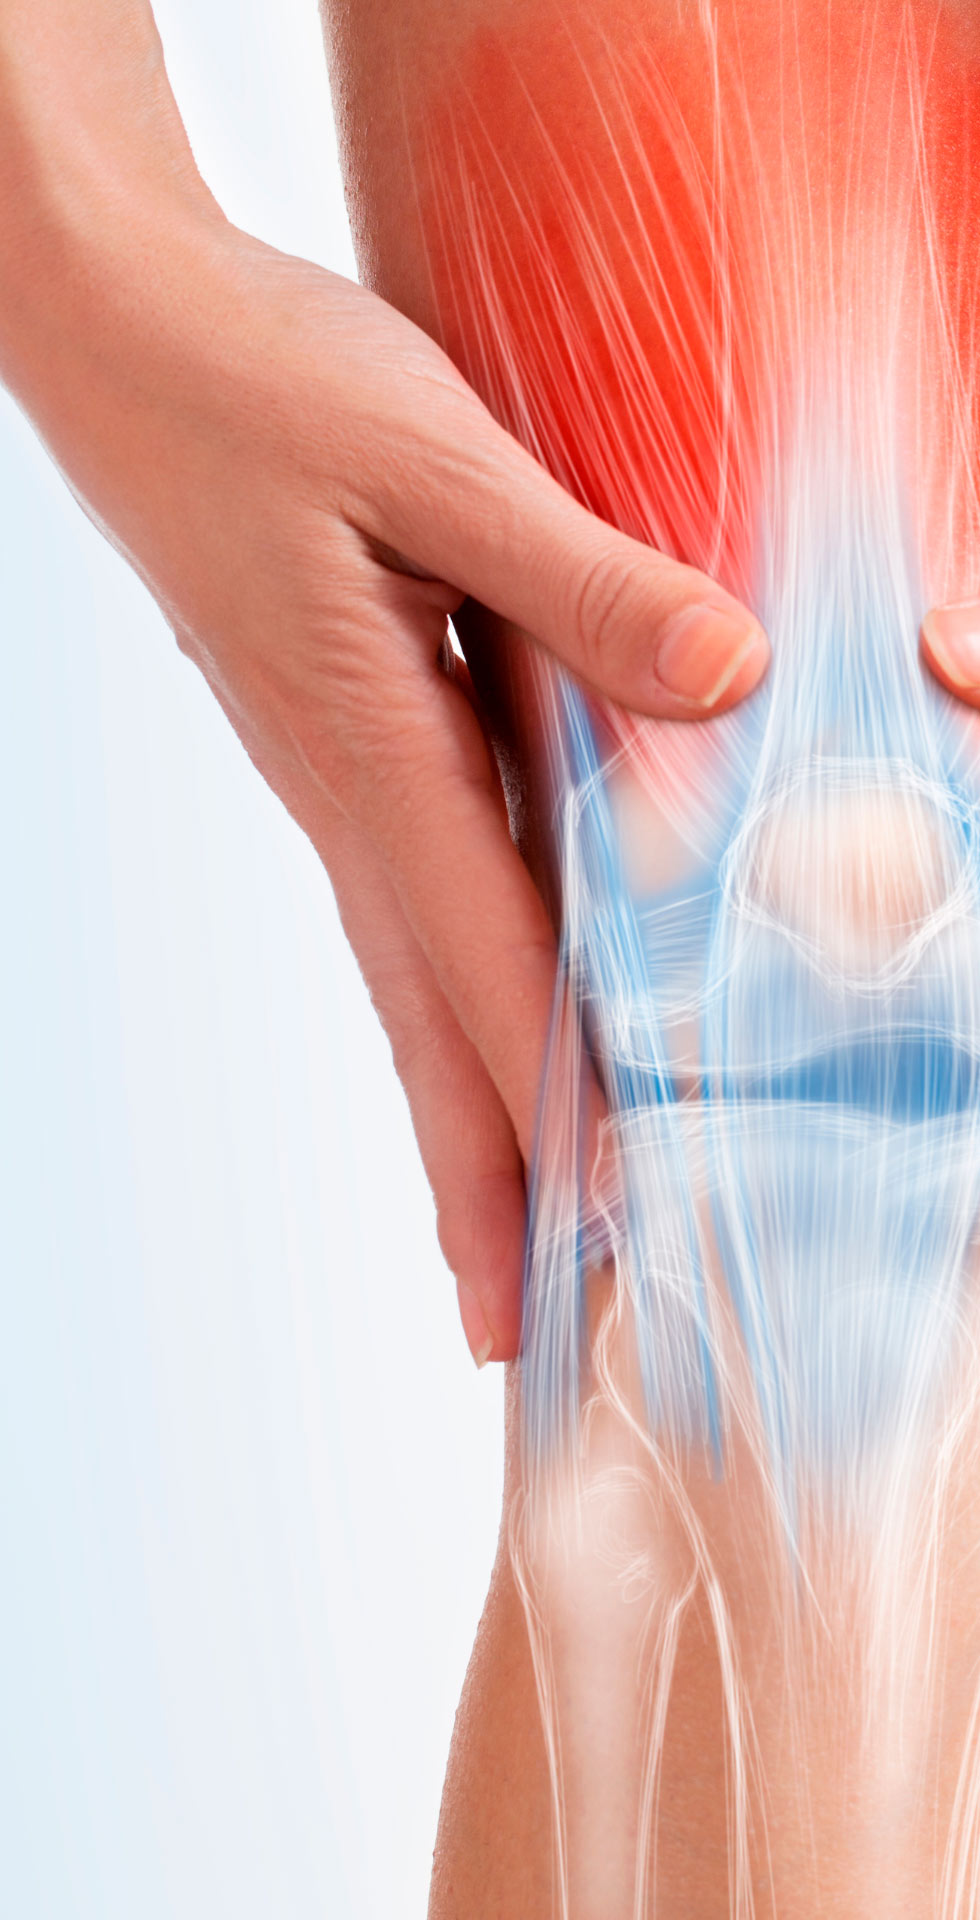

Many people immediately reach for a knee brace when they feel pain, but using it without supervision

can cause more harm than good.

Before making it your everyday companion, it’s important to understand the risks.

Knee injuries often lead to pain, swelling, odd sounds, instability, and limit everyday activities like walking, running, or even working.

Our goal is to help you fully recover your knee functionality so you can move freely and without limitations